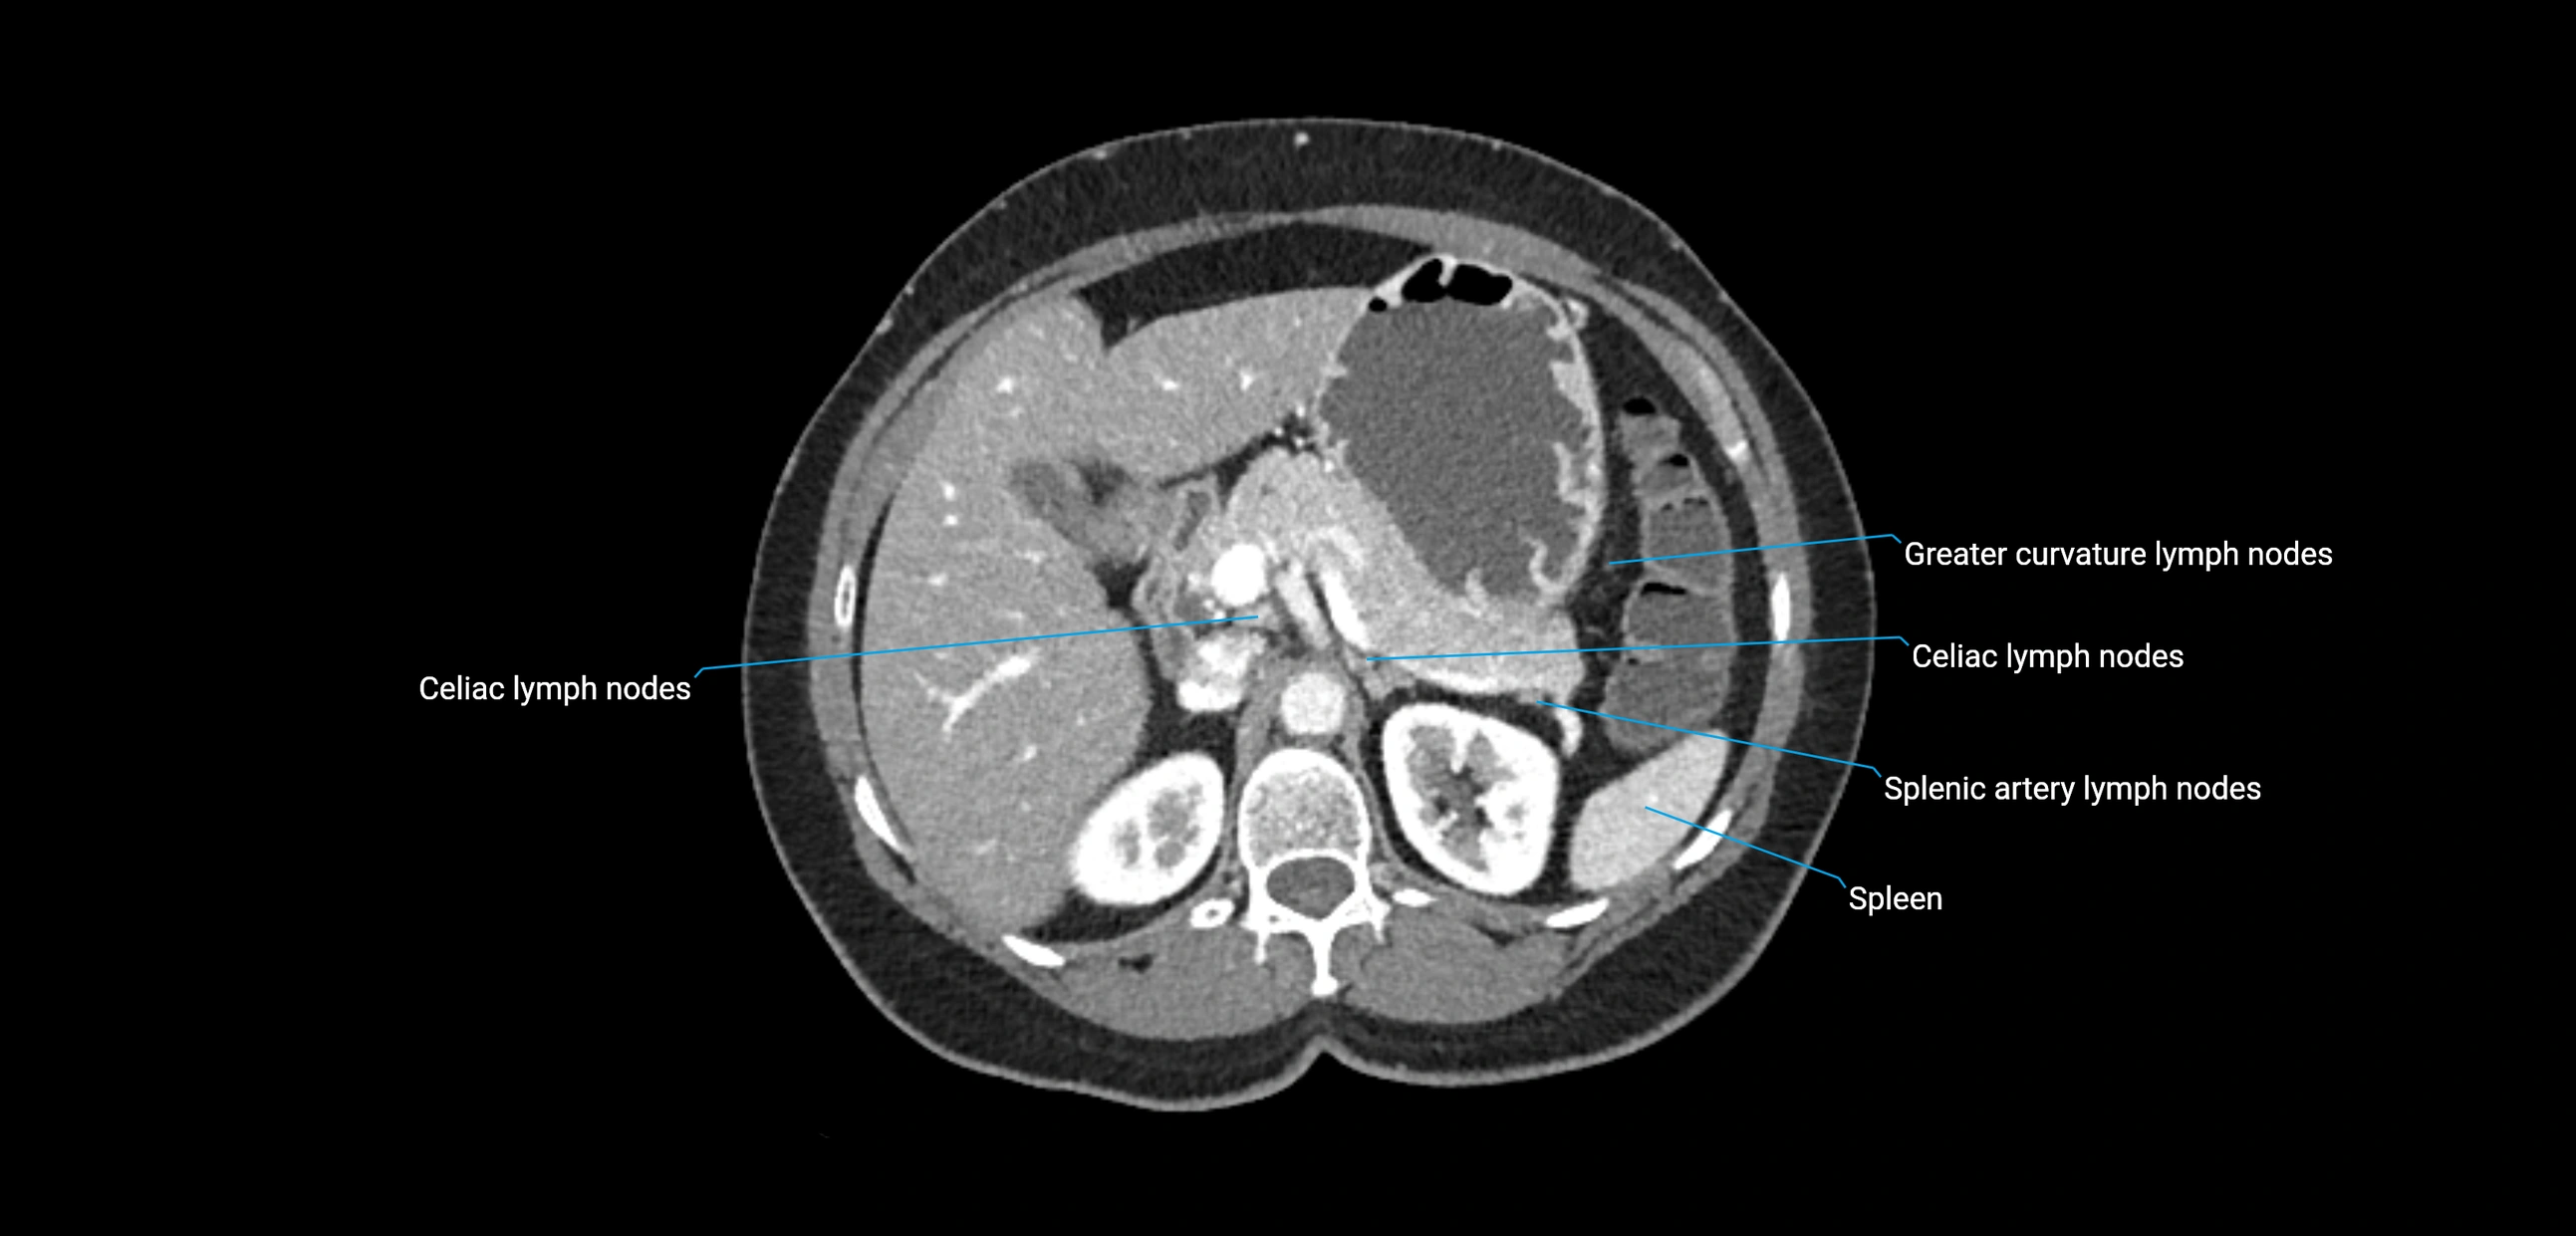

CT Appearance

CT Post-Contrast:

• Normal nodes enhance homogeneously

• Malignant nodes may show heterogeneous enhancement, central necrosis, or conglomerate formation

• Size >1 cm short axis is suspicious, though morphology and distribution are equally important

CT Venography (CTV):

• Demonstrates nodal encasement or compression of adjacent vessels (aorta, IVC, renal veins)

• Useful in staging testicular and ovarian malignancies

• Provides 3D reconstructions for retroperitoneal lymph node dissection planning